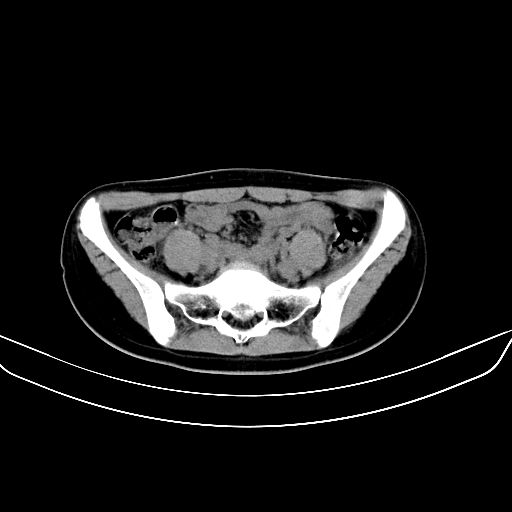

以下是引用zsl6918在2008-7-11 21:40:00的发言:[br]双侧骶髂关节骨质破坏以下三分之一为主,符合强直性脊柱炎表现

以下是引用zhangzhongshou在2008-7-11 21:41:00的发言:[br]患者是女性,hla-b27抗原(—),首先不太考虑强直性脊柱炎,建议查类风湿因子,骶髂关节改变考虑类风湿性关节炎可能性大,建议进一步检查。